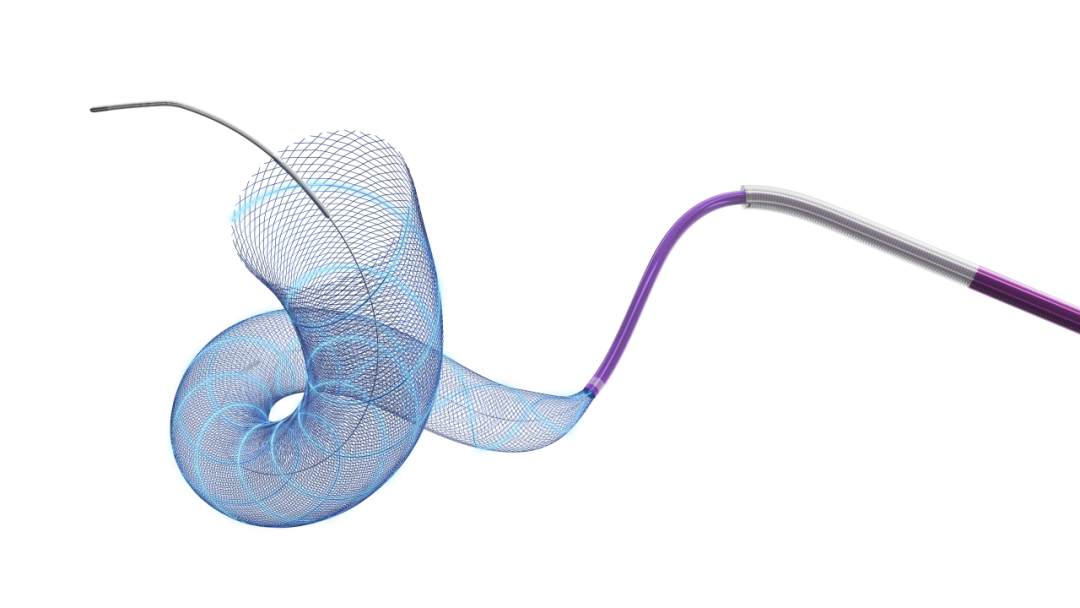

Tubridge Plus血流导向密网支架 4.5mm*25mm

Fastrack支架微导管到达动脉瘤以远,经Fastrack支架微导管释放4.5mm*25mm Tubridge Plus血流导向密网支架,支架锚定于动脉瘤远端,后保持微导管张力与支架推送力的动态平衡,缓慢推送释放支架,覆盖病变血管。

调整微导管张力,缓慢释放Tubridge Plus支架尾部,支架完全打开,撤出推送导丝。

使用J型导丝在支架内按摩,促使Tubridge Plus支架每个节段与血管良好贴壁。

Tubridge Plus是“两维3D”、全程显影的密网支架。采用含铂芯的镍钛复合材料DFT丝编织而成,支架的每根编织丝都全程显影,同时两根双螺旋显影丝强化了支架局部贴壁效果,极大提升了颅底部位的可视性、更好地判断支架打开和贴壁的情况。

手术过程中支架头端锚定性好,打开释放过程顺畅,推送顺滑。术后随访能够达到动脉瘤完全闭塞,支架内无明显狭窄。